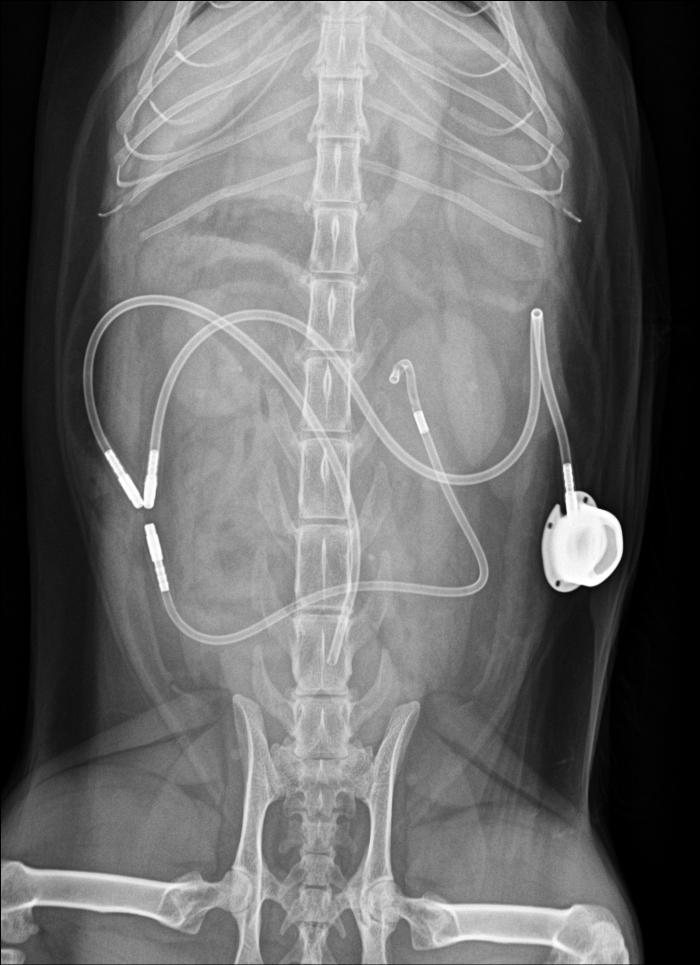

- Suelen requerir intervención quirúrgica urgente, por ejemplo, mediante la colocación de stents o bypass ureterales subcutáneos (SUB) (Figura 1-2) (ambas imágenes han sido cedidas por el Servicio de Diagnóstico por Imagen del Hospital Veterinario Puchol), pero también requieren una estabilización mínima previa a la anestesia.